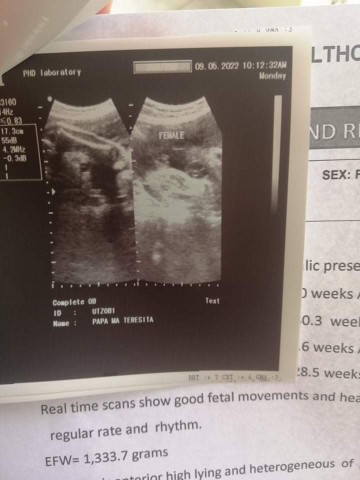

BOY o Girl?

gender check

tingin nyo po girl or boy?